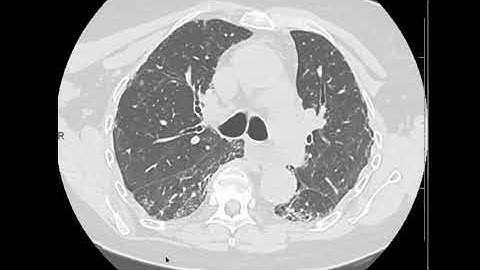

Nonspecific interstitial pneumonia (NSIP): multiple examples with typical imaging patterns